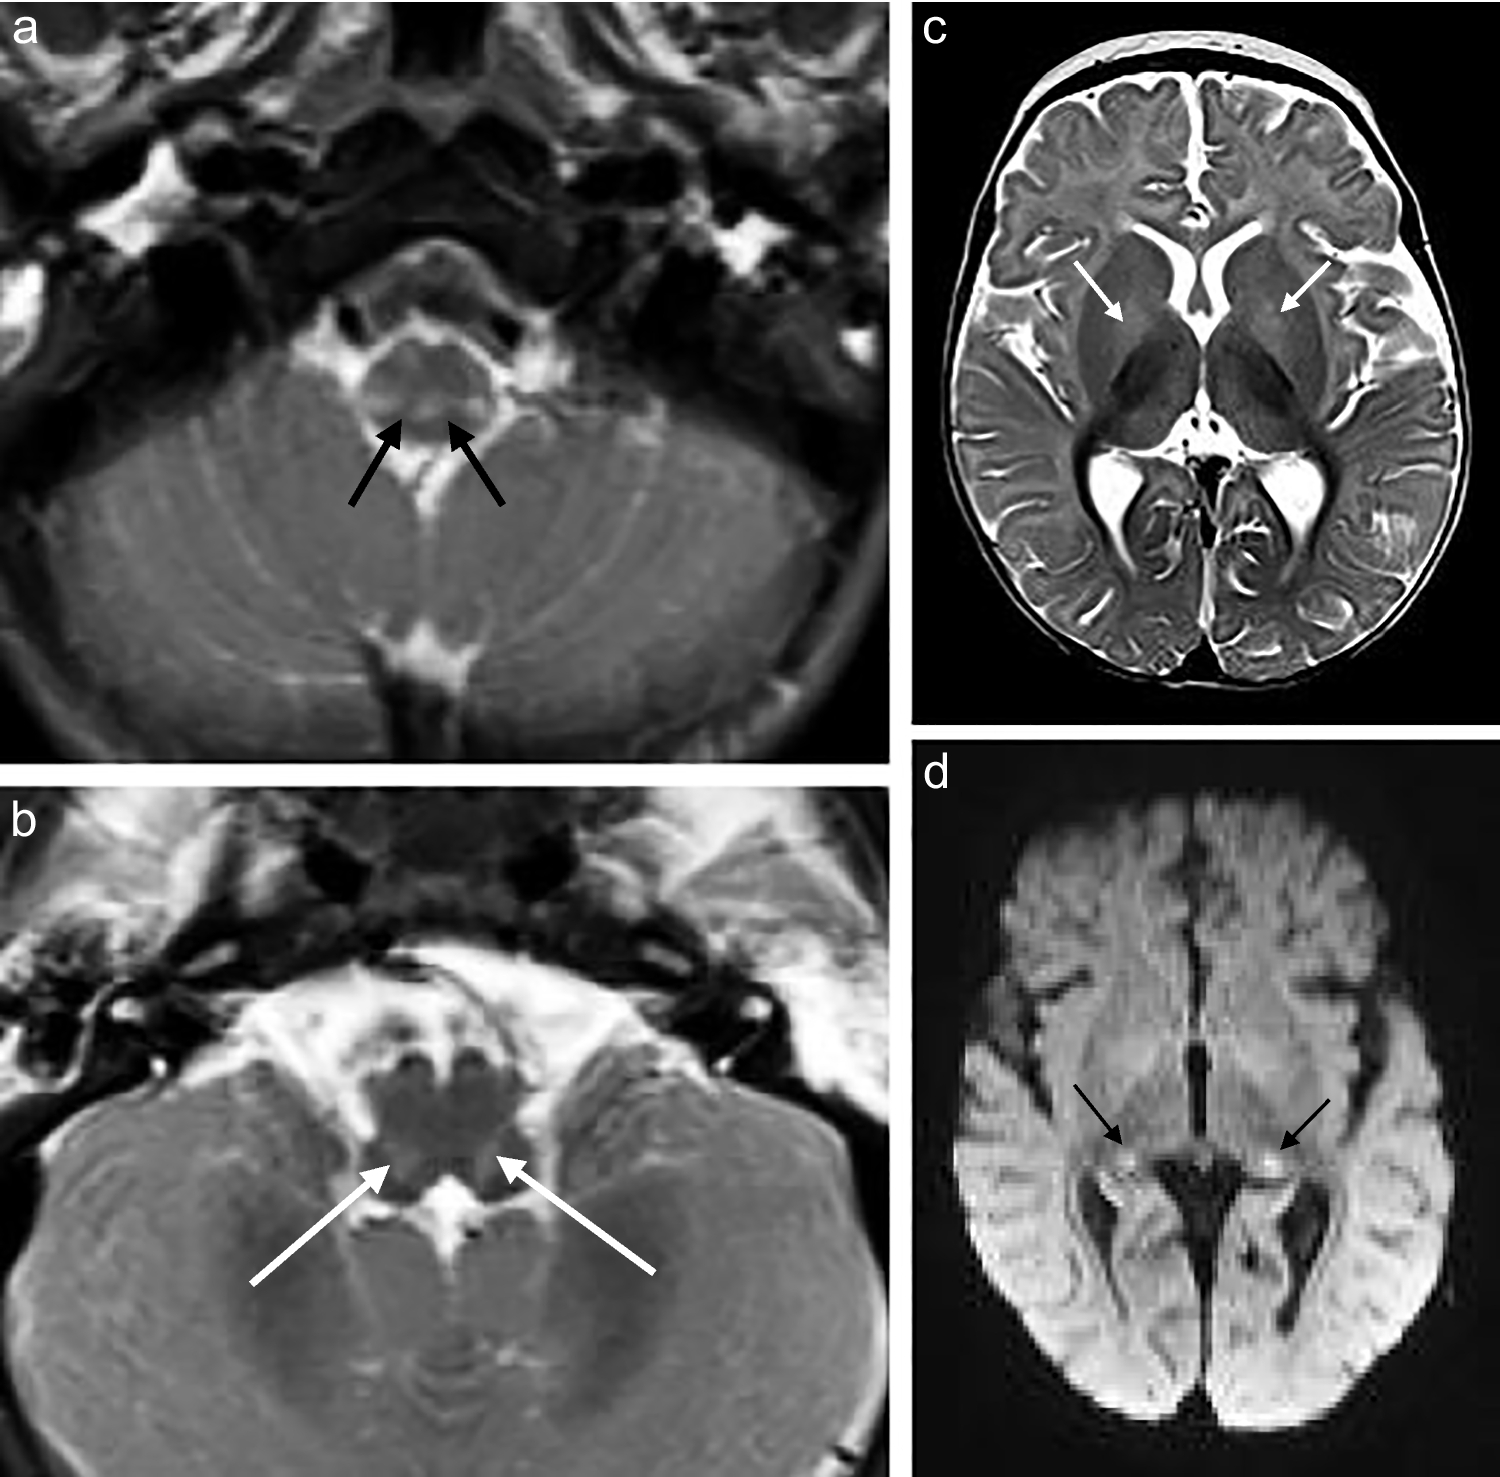

A 2-week-old boy with genetically confirmed MPV17-related mitochondrial depletion syndrome. a Axial T2-weighted image shows hyperintense signal in the reticulospinal tracts of the proximal cervical cord (arrowheads). b Axial diffusion-weighted image and (c) apparent diffusion coefficient map demonstrate restricted diffusion in the cerebral peduncles (arrows). d Axial diffusion-weighted image and (e) apparent diffusion coefficient map demonstrate restricted diffusion in the globus pallidi (arrows). f Axial diffusion-weighted image and (g) apparent diffusion coefficient map demonstrate restricted diffusion in the subperirolandic white matter (arrows). h Axial diffusion-weighted image shows restricted diffusion in the medullary pyramidal tracts (arrows)

Fig. 4

A 4-month-old female with genetically confirmed MPV17-related mitochondrial depletion syndrome. a Axial T2-weighted image shows hyperintense signal in the reticular formation of the medulla (arrows). b Axial T2-weighted image shows hyperintense signal in the posteromedial globus pallidi (arrows)

Fig. 6

An 8-month-old girl with genetically confirmed MPV17-related mitochondrial depletion syndrome. a Axial T2-weighted image shows hyperintense signal in the reticular formation of the medulla (arrows). b Axial T2-weighted image shows hyperintense signal in the central tegmental tracts of the pons (arrows). c Axial T2-weighted image shows hyperintense signal in the cerebral peduncles of the midbrain (arrows). d Axial diffusion-weighted imaging and (e) apparent diffusion coefficient maps confirm restricted diffusion symmetrically present in the subperirolandic white matter (arrows). f Axial diffusion-weighted imaging shows restricted diffusion in the cerebral peduncles (arrows). g Axial diffusion-weighted imaging shows restricted diffusion present within the white matter (asterisks), posterior limbs of the internal capsules (white arrows) and cingulate gyri (black arrows). h DWI image shows restricted diffusion in the optic tracts and olfactory nerves (arrows) (i). j Axial T2-weighted image shows hyperintense signal in the medial globus pallidi (arrows)

Brainstem

The brainstem was affected in four of eight (50%) patients and all signal changes were topographically localised to white matter tracts (Figs. 2 and 6). The 11-day-old had signal alteration conforming to the rubrospinal tracts in the midbrain. The 2-week-old had abnormal signal conforming to the corticospinal tracts traversing the cerebral peduncles of the midbrain and medullary pyramidal tracts of the ventral medulla. Both 8-month-old infants manifested T2 hyperintense signal in the cerebral peduncles as part of corticospinal tract involvement. Restricted diffusion accompanied white matter tract signal abnormality in all but one case.

Only one of the seven patients with T2 hyperintense changes in the reticular formation had associated restricted diffusion which localised to the central tegmental tracts of the pons. Restricted diffusion in the diseased parts of the brain accompanied most extra-reticular MRI abnormalities, occurring in five of eight patients (62.5%) (Figs. 1, 2, 5, 6 and 7). The ADC values ranged from 431 × 10–6 mm2/s to 845 × 10–6 mm2/s with a mean value of 579 × 10–6 mm2/s. The ADC values tended to be lowest when acquired in the diseased white matter.

Cranial nerves and nuclei

Half of the patients (50%) showed signal disturbances in these regions. One neonatal MRI revealed restricted diffusion in the midline tegmentum, near the oculomotor nuclei of the midbrain (Fig. 2). Three of the older infants’ (5 months to 8 months) MRI scans all demonstrated restricted diffusion in the optic chiasms and tracts, fornices, and olfactory nerves (Fig. 6).